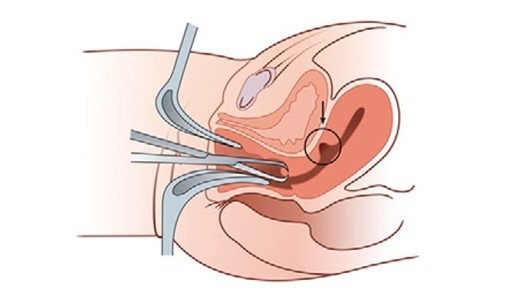

剖宫产术后的憩室处本身就是子宫的薄弱之处,肌层菲薄,再次怀孕可能会导致憩室处妊娠或是孕期子宫破裂等。所以,如果有再次生育的要求,可以选择宫腹腔镜联合手术,也可以选择经阴道手术+宫腔镜手术。目的都在于切除疤痕憩室,彻底修复子宫。但这种手术的远期效果暂时也不是很明确,可能切口再次愈合不佳,憩室再次形成,症状又再次出现。同时手术后也还需要等上1-2年才能再次妊娠。手术后的王女士月经也渐渐得到了改善,但远期疗效如何她还是有着一定的顾虑。